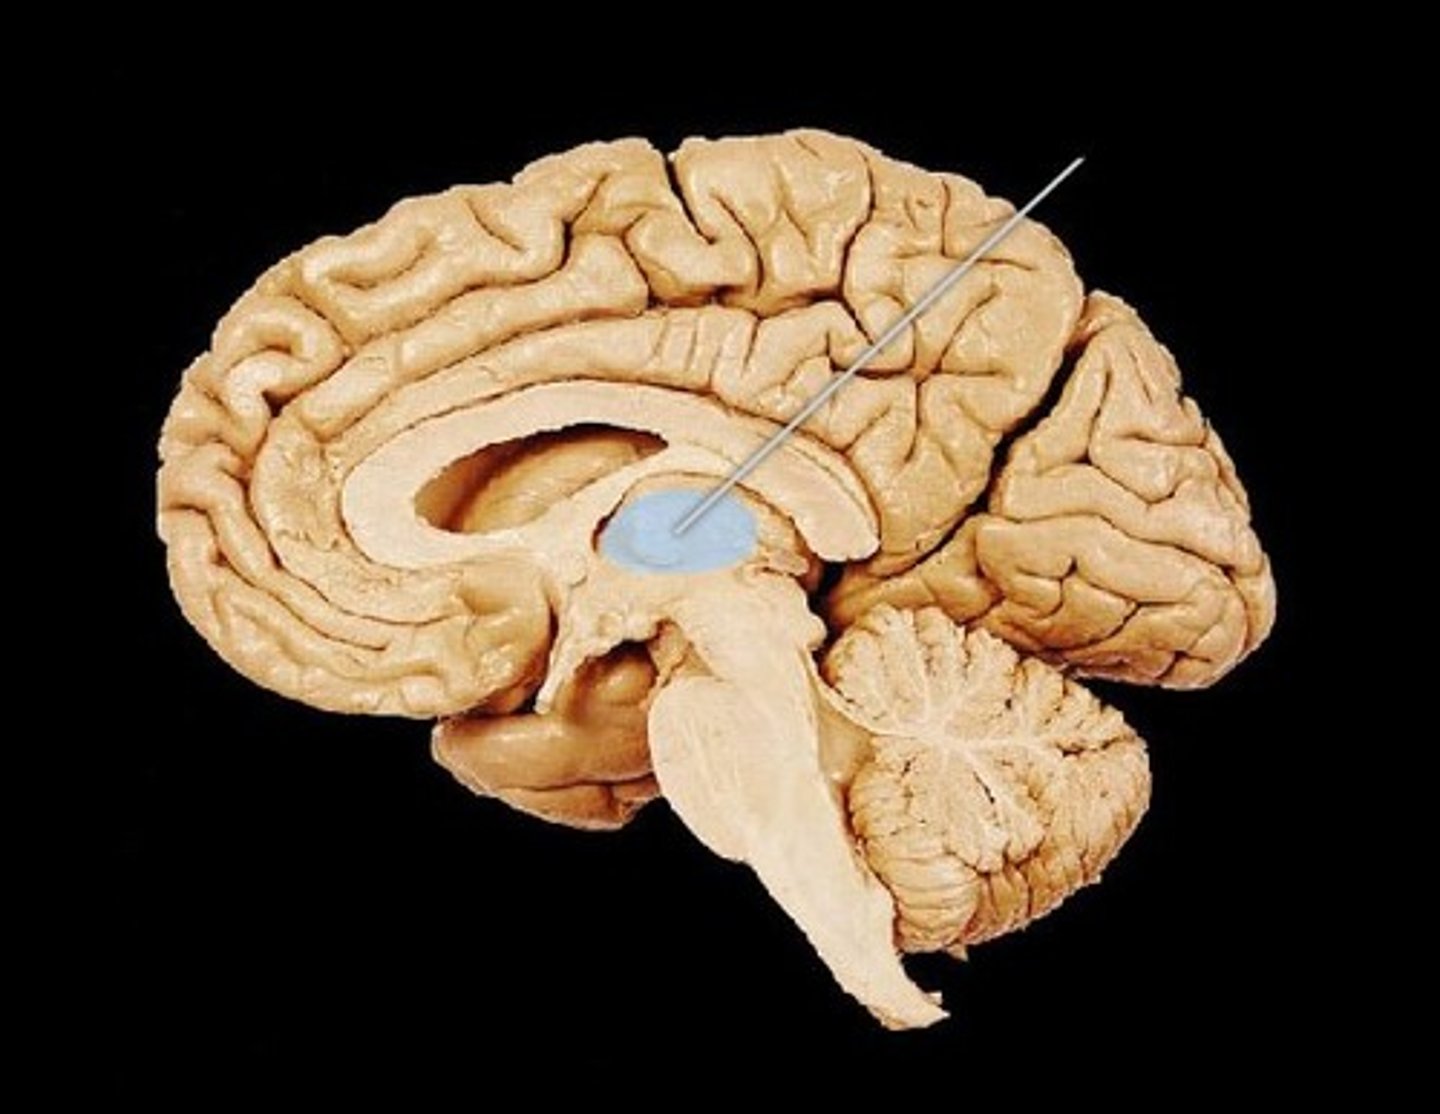

corpus callosum

lateral ventricles

3rd ventricle

thalamus

hypothalamus

midbrain

pons

medulla oblongata

cerebral aqueduct